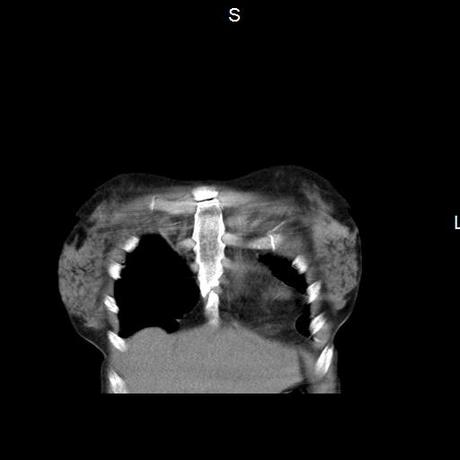

Se realiza volumen de tórax en fase simple, desde los opérculos torácicos hasta los hemidiafragmas, observándose:

La tráquea es central, con adecuada columna de aire, sin evidencia de compresiones o desplazamientos.

El mediastino es central, sin evidencia de crecimientos ganglionares.

El corazón y los grandes vasos de morfología y situación normal.

El parénquima pulmonar con areas parcheadas difusas en vidrio despulido combinadas con otras areas hipodensas de baja atenuación debidas a atrapamiento aéreo y engrosamiento intersticial y zonas de fibrosis de predominio en lóbulos medios e inferiores de ambos pulmones.

- LOS HALLAZGOS PUEDEN ESTAR EN RELACIÓN A NEUMOPATIA INTERSTICIAL PROBABLE ETIOLOGIA HIPERSENSITIVA VS AUTOINMUNE/BACTERIANA/FUNGICA.